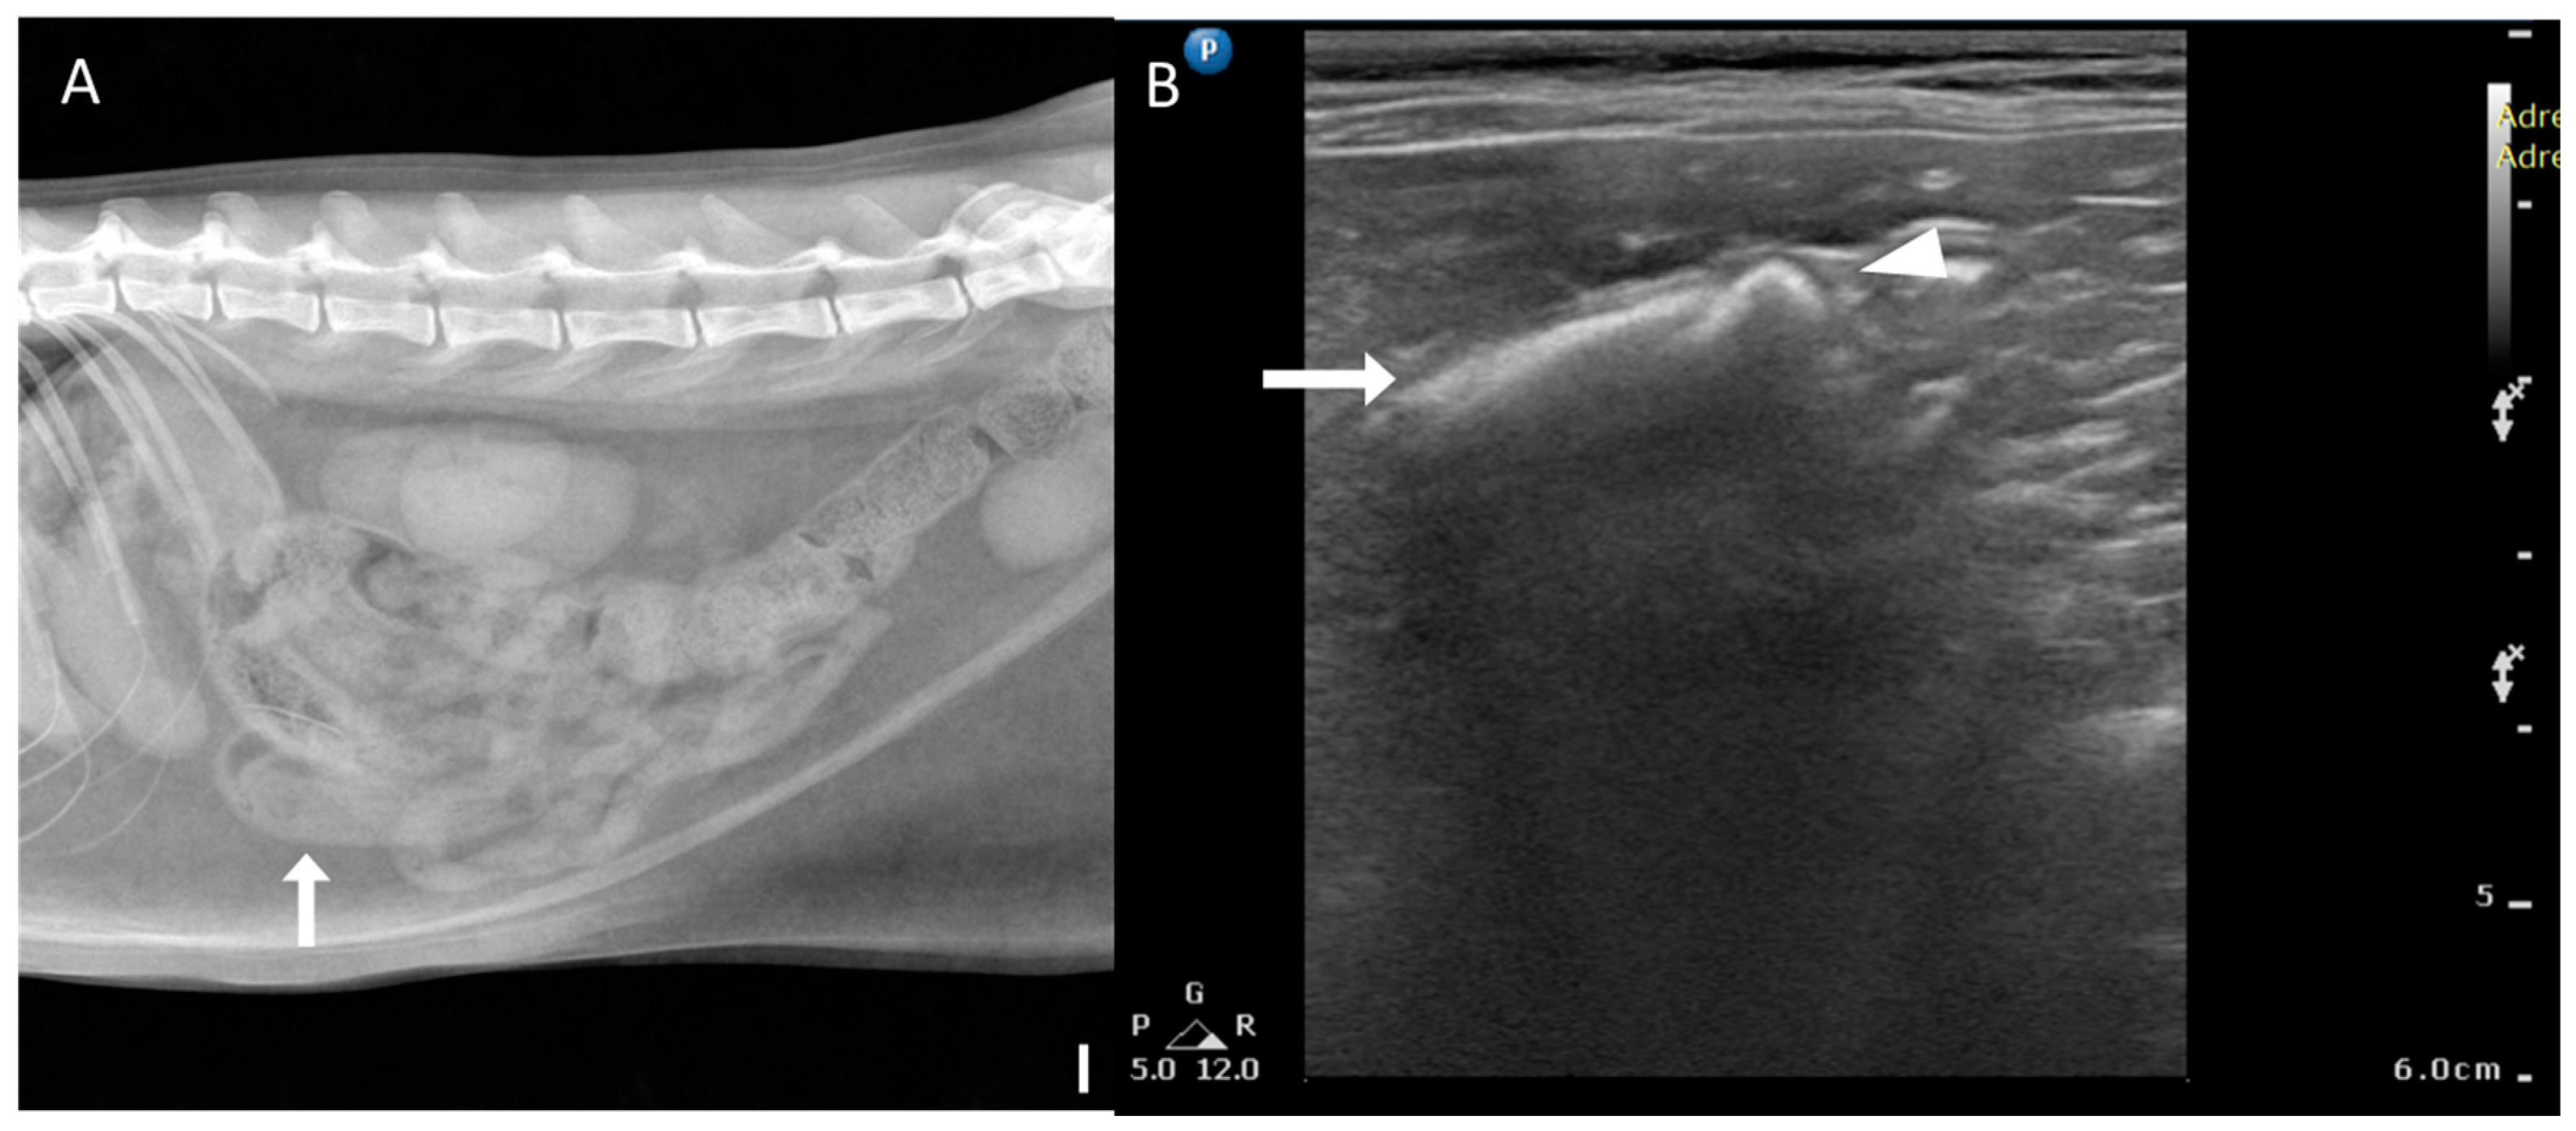

3.3. Radiographic and Ultrasonographic Characteristics of Bezoar

Radiographic and US findings of bezoars are summarized in Table 2. Foreign bodies (1/6, 16.7%) with a mottled and solid appearance (Figure 6) were identified in only one case using radiography. Nonspecific signs of mechanical obstruction, such as small intestinal dilation, were observed in most cases (5/6, 83.3%). On US, acoustic shadowing was detected in most cases (4/6, 66.7%), and a heterogeneous surface (Figure 6) was noted in areas suspected of containing foreign bodies. In two cases, acoustic shadowing was absent. All cases exhibited dilation of small bowel segments, which is a nonspecific indicator of small bowel obstruction.

Figure 6. Radiographic and ultrasonographic features of bezoars. (A) Right lateral radiograph (scale bar equals 1 cm) of a patient with a trichobezoar. Focal small intestinal dilation and a mottled solid appearance are observed in the small intestine (arrow). (B) Ultrasonographic image of the same patient as in (A), showing a heterogeneous surface with mixed hypoechoic and hyperechoic parenchyma (arrow) in the impacted segment. A trichobezoar in the jejunum is seen with acoustic shadowing (arrowhead).